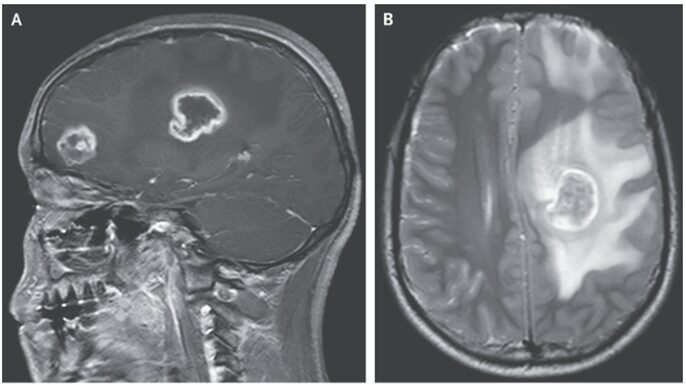

頭部MRIにて精査されT1強調画像、sagittalにて前頭葉における病変を認め(A)

T2強調、axial画像にて病変と周囲の浮腫像、および正中線のシフトが確認された(B)